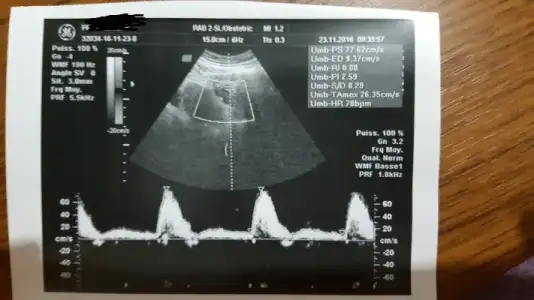

Histereskopiden mi bu kadar gecikti ovu yine uzuuuunnn adet döngülerim mi baş gösterdi onu da anlamadım..

Eki Görüntüle 1916074

Eki Görüntüle 1916074